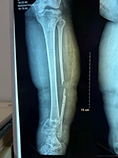

Acute osteomyelitis

Acute osteomyelitis can be a devastating or even fatal disease with a high rate of sequelae, especially in resource-poor countries. AHOM is typically a monomicrobial disease, Staphylococcus aureus (S. aureus) remains the most common pathogen globally notwithstanding that Methicillin-resistant Staphylococcus aureus (MRSA) has an increased.

Early diagnosis is the key to successful management and the prevention of long-term sequelae.

the management for AHOM includes Empiric IV (intravenous) antibiotics based on the most likely causative agents, Source control: specimens for microscopy, culture and sensitivity (MCS).

If there is no response to medication within days, an intervention such as draining an abscess might speed up the healing process, A corticotomy can be performed for intraosseous collections, and drains are routinely placed. Bone drilling is required in patients with subperiosteal or intramedullary abscesses

The limb segment should be protected in the first six weeks to prevent a pathological fracture.